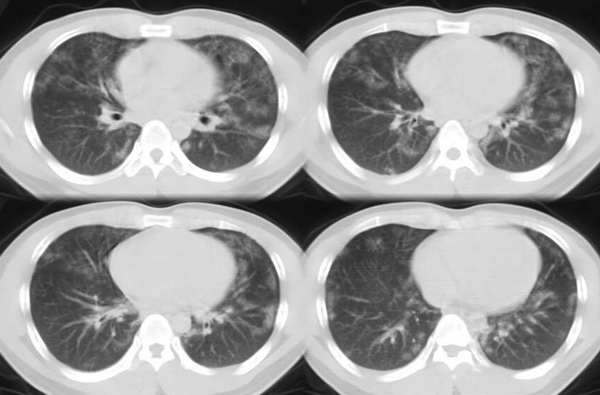

以下是引用ssl1_1在2006-3-2 22:37:00的发言:[br]肺泡蛋白沉积症(外围型)

以下是引用huangaiying1在2006-3-3 16:03:00的发言:[br]双肺弥漫分布的磨玻璃影及小结节影,以双上肺为著,纵隔内未见明显增大的淋巴结影,结合病史,考虑过敏性肺炎

以下是引用guandong在2006-3-4 20:57:00的发言:[br]两肺弥漫分布磨玻璃影,以中外带为主,可见于过敏性肺炎、肺泡蛋白沉着症、农民肺等,但不支持结核。